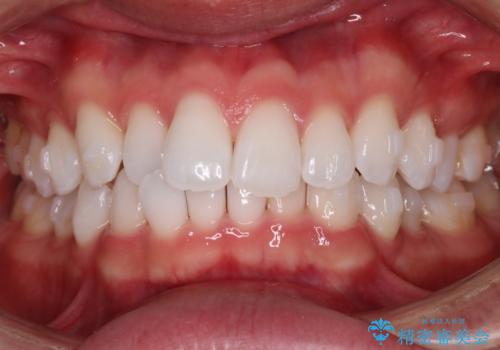

治療症例の内容

- 患者様

- 20代男性

- 矯正装置

- インビザライン

- 治療期間

- 1年

- 治療回数

- 5-10回

- 治療計画

- がたつきが気になるとの事で来院されました。

目立たない装置で費用も抑えたいとの希望があったため、インビザラインにて治療をすることとなりました。

上下顎ともにIPR(歯と歯の間を削る処置)を行い歯並びを整える治療計画を立てました。

治療当初は、計画通りに治療が進むか心配でしたが、しっかりマウスピースを使用していただいたことで

治療期間も長引くことなく歯並びを綺麗に改善することが出来ました。

患者様の希望もあり、前歯の微調整で1回リファイメント(マウスピースの再発注)を行いました。

患者様の希望に沿う治療を提案することができ良かったと思います。